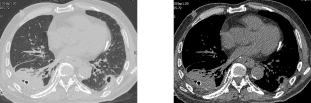

术后1月胸部CT(肺窗) 纵膈窗